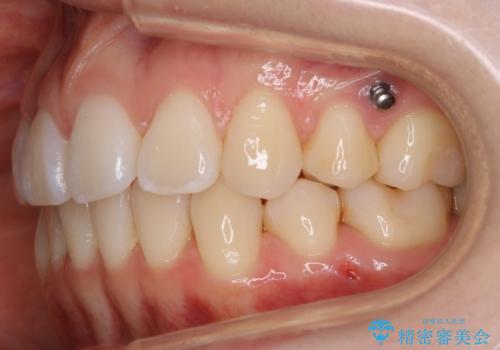

- マウスピース(インビザライン)

- 1年6ヶ月

- 税込 ¥968,000- (インビザライン コンプリヘンシブパッケージ + マイクロインプラント費用)費用は治療当時の料金となります